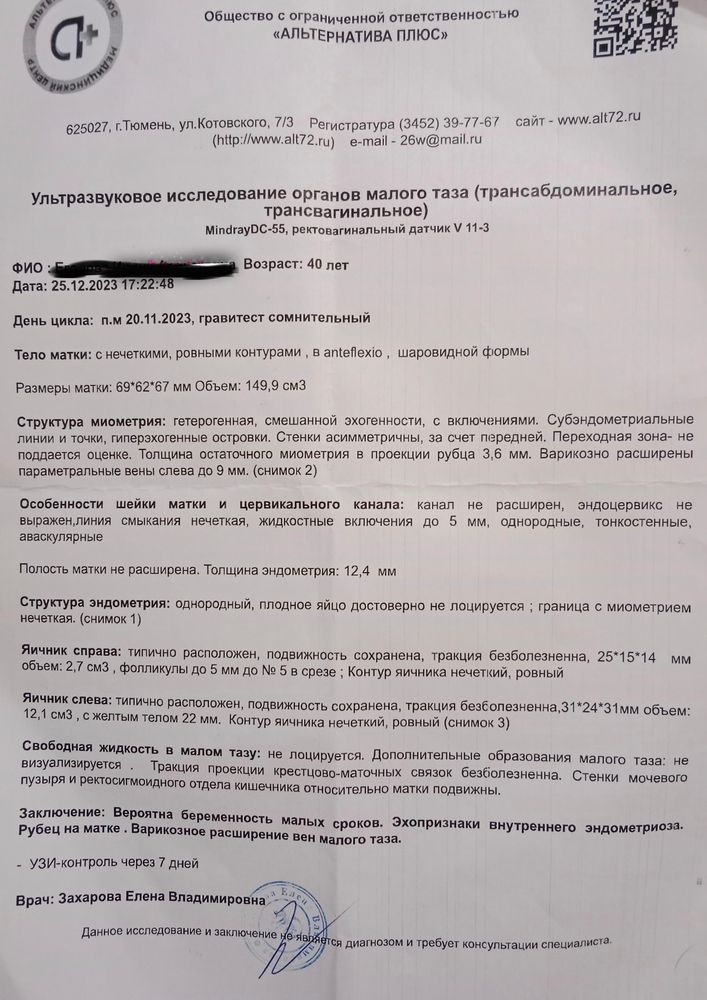

Забежала после работы на узи

Аня, сделала узи сегодня фото добавила

Завтра утром иду к врачу

Аня, да сходила по месячным беременность 7 недель по Узи только 5, гинеколог сказала было две овуляции с разных сторон.

а спермии оказывается могут гулять от недели до 2х

Dina, в нашем случае именно вторая овуляция сыграла роль, такой вот сбой дал мой организм, поэтому сейчас отличается срок по узи и акушерский

Dina, первая овуляция была справа но не оплодотворилась и там остатки желтого тела которое начало распадаться.

Слева была втора овуляция причем она была по срокам на 2 день задержки.

Гинеколог сказала что так бывает особенно у женщин старше 40 организм так пытается повысить шанс оплодотворения. Были случаи когда оплодотворялись обе яйцеклетки но это редкость.